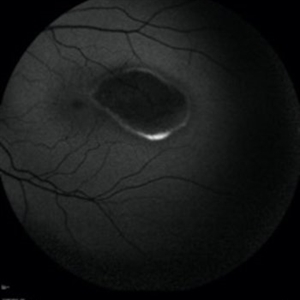

Fundus photograph of an asymptomatic 12-year-old girl with torpedo maculopathy of the left eye.

Photographer: Pierre-Henry Gabrielle, Ophthalmology department, Dijon University Hospital, France

Imaging device: Zeiss visucam

Condition/keywords: fundus photograph, torpedo maculopathy